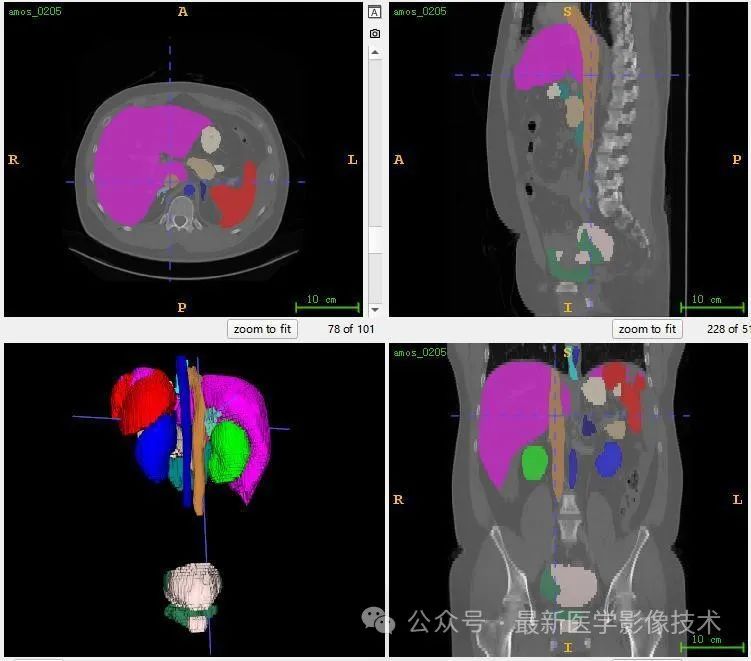

13、测试集分割结果

12、验证集分割结果

左图是金标准结果,右图是预测结果。